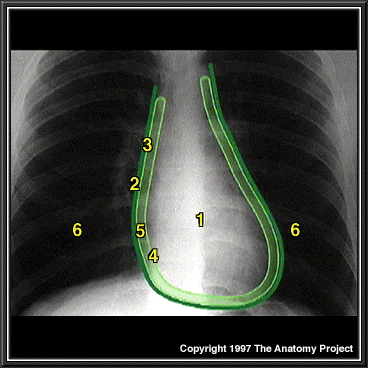

Chest XÐray showing pericardium, posteroanterior view

Heart

Fibrous pericardium

Parietal layer of serous pericardium

Visceral layer of serous pericardium

Pericardial space

Pleural cavity and lung